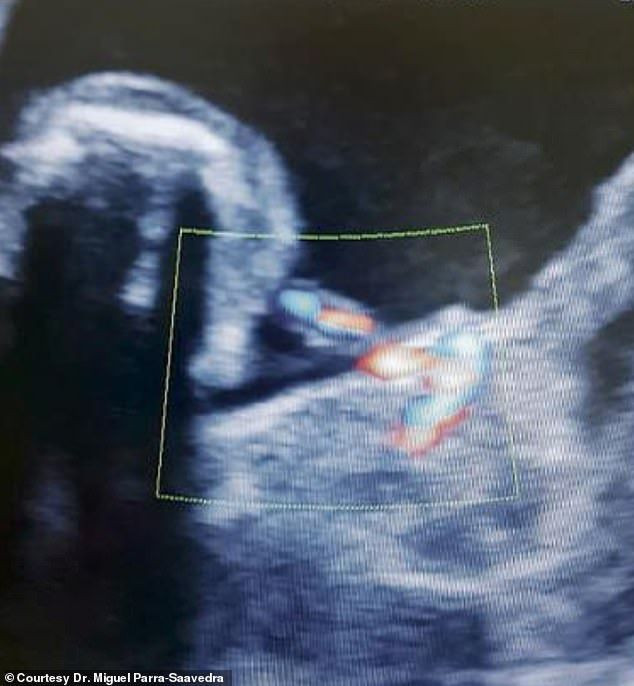

KOLOMBİYA'da eşine az rastlanır bir doğum yaşandı. Anne karnındaki bebek kardeşini kendi karnında taşıdı.

Barranquilla kentinde yaşan genç bir kadın doktor kontrolü için muayeneye gitti. Ancak doktor bebeğin karaciğerinde kist olmasından şüphelendi. Bunun üzerine muayene derinleştirildi ve bebeğin içinde kist değil bir bebek olduğu öğrenildi.

Doktorlar ilk olarak 1808’de kayıtlara geçen ‘fetüs içinde fetüs’le karşı karşıya olduklarını anladı. Bebek içindeki bebeğin alınması için doğum anı beklendi. Anne hamileliğin 37’nci haftasında kızı Itzmara’yı sezaryenle dünyaya getirdi. 22 Şubat’ta doğan Itzmara bir gün sonra ameliyat edildi.

Bebeğin karnındaki 45 milimetre boyunda 14 gram ağırlığında olan ikiz kardeşi alındı. Kolları ve bacakları olan ancak kalp ve beyni olmayan bebek göbek bağı kesilir kesilmez öldü.

Doktor Parra-Saavedra “Teorik olarak Itzmara kendi kardeşine hamileydi” dedi. Parra-Saavedra bir aylık olan bebeğin sağlık durumun iyi olduğunu söyledi.